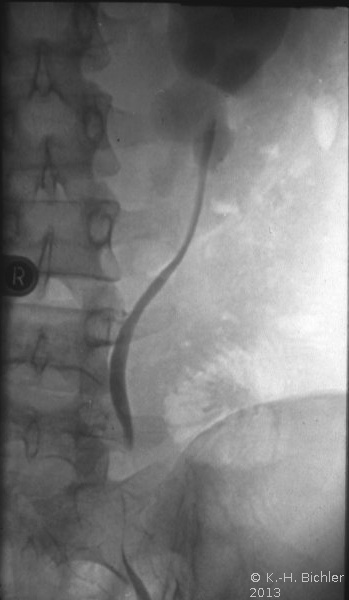

Die retrograde Sondierung gab Hinweis auf ein strangulierendes Hindernis im Bereich des Harnleiterabgangs (aberrierendes Gefäß, Bride?). Das retrograde Pyelogramm zeigte ein erweitertes, aber sonst unauffälliges NBKS (Abbildung 6).